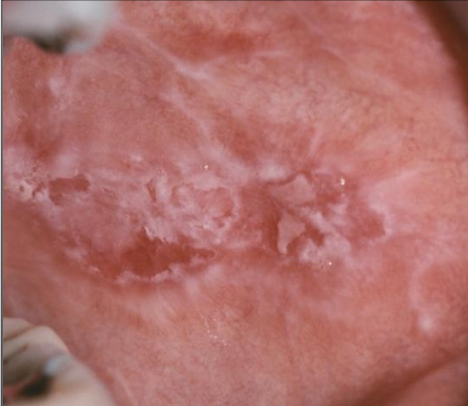

What is reticular lichen planus?

More common, asymptomatic, lace-like (Wickham striae)

White lace-like striations (Wickham striae), maybe erythematous, bleeding

Buccal mucosa, gingiva, tongue, lip